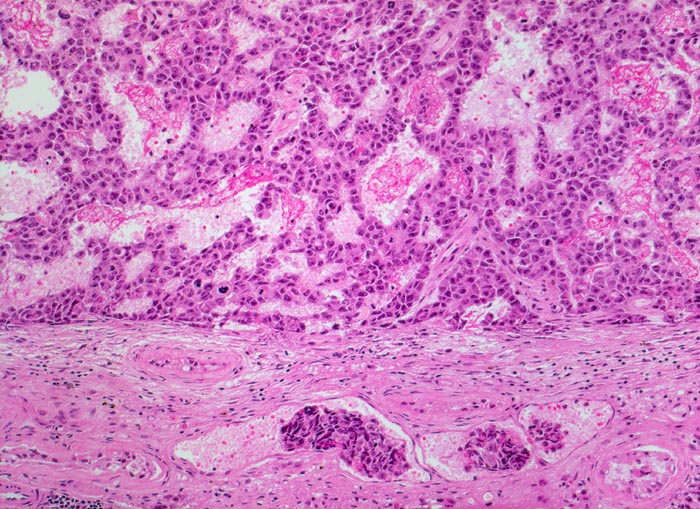

Embryonales Karzinom des Hodens: Gefässeinbruch

Polymorphe Tumorzellen bilden miteinander anastomosierende Stränge. Nachweis von Tumorzellgruppen in dünnwandigen Gefässen.

Makroskopisch aus mehreren unscharf begrenzten, bunten, teils hämorrhagischen Knoten bestehender Tumor von 3cm Durchmesser.

Die Blutgefässinvasion hat bei Hodentumoren einen Einfluss auf das TNM Stadium und somit auf die Prognose. Embryonale Karzinome zeigen häufiger eine Gefässinvasion als Seminome.